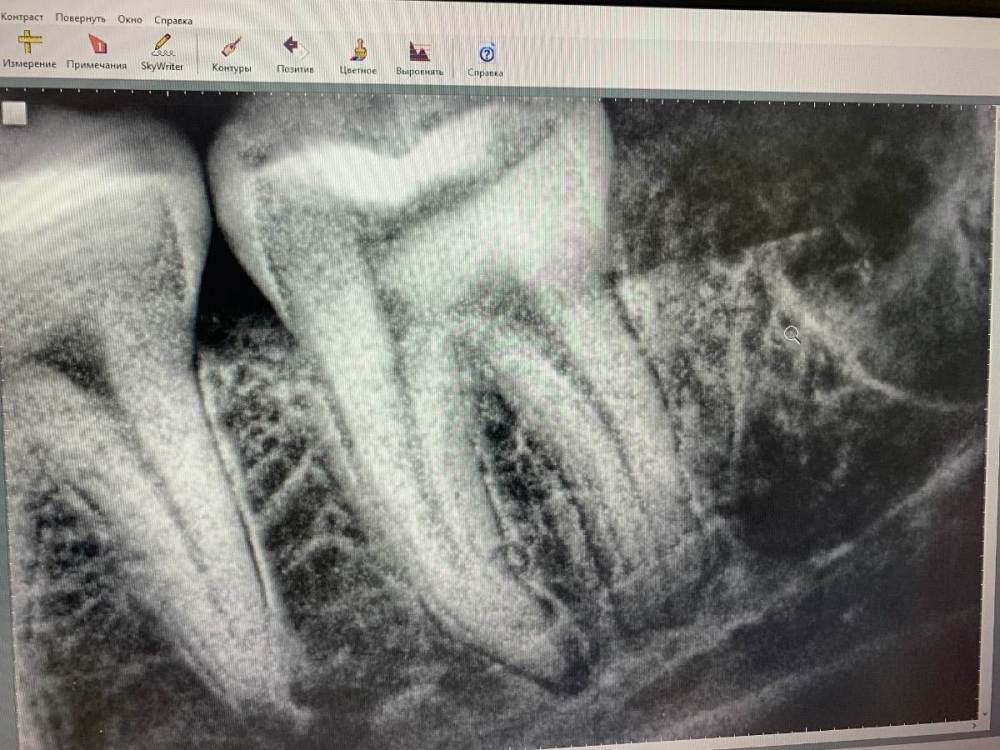

Nadezda79 Опубликовано 11 апреля, 2022 Автор Поделиться Опубликовано 11 апреля, 2022 Здравствуйте! С момента удаления прошел месяц. Полторы недели я ходила на промывку лунки и перевязки. Но пару дней назад возобновились болевые ощущения (не сильные) преимущественно под вечер в области лунки и семерки, челюсти под ней. Так же до сих пор присутствует онемение части щеки. Уважаемые врачи, что вы можете сказать по поводу снимка? Ссылка на комментарий

Irouil Опубликовано 11 апреля, 2022 Поделиться Опубликовано 11 апреля, 2022 Снимок не полный, но в той части лунки, которую он охватывает, ничего настораживающего не вижу Ссылка на комментарий

red_butler Опубликовано 12 апреля, 2022 Поделиться Опубликовано 12 апреля, 2022 Я бы проверил 7 зуб на витальность, по снимку на периодонтит похоже Ссылка на комментарий